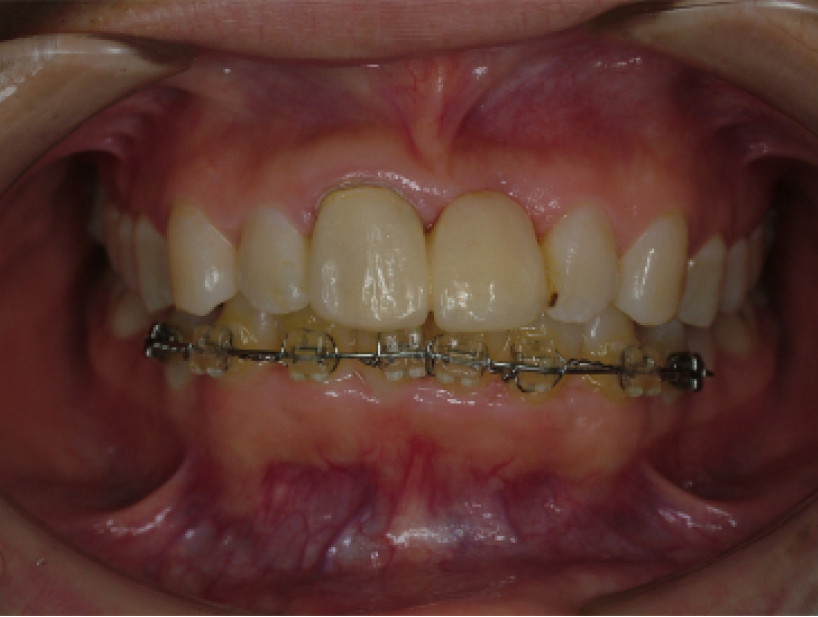

治療前治療後

| 治療内容 | インプラント奥歯1本 |

|---|---|

| 患者様の年齢 | 48歳 |

| 患者様の性別 | 男性 |

| 治療期間 | 5ヶ月 |

| 治療回数 | 25回程度 |

| 治療費用 | 50万円 |